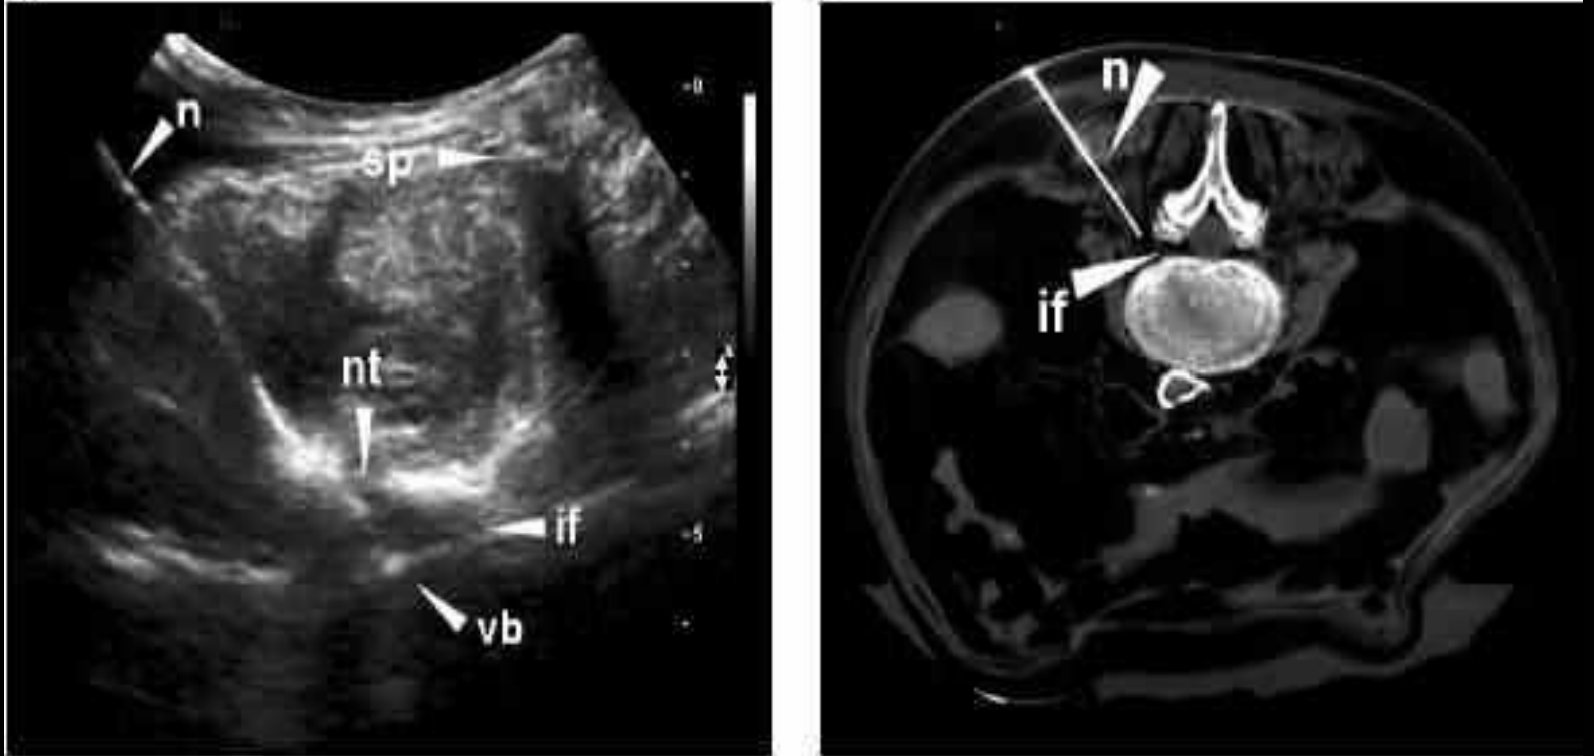

比如我们科室的“王牌手段”——超声引导下神经阻滞/注射治疗。很多患者担心“打封闭有副作用”,但疼痛科的注射和普通“封闭”完全不同:我们会用超声精准定位压迫神经的“靶点”,把消炎镇痛药物直接送到炎症部位,像“精准投送”一样缓解神经水肿,既能快速止痛,又能减少药物对全身的影响。上周有位40岁的上班族,腰痛伴左腿麻1个月,走路都得扶腰,超声引导注射后3天,麻痛感就减轻了大半,现在已经能正常上班。

“超声引导:像‘导航’一样找到疼痛根源,微创更安全”